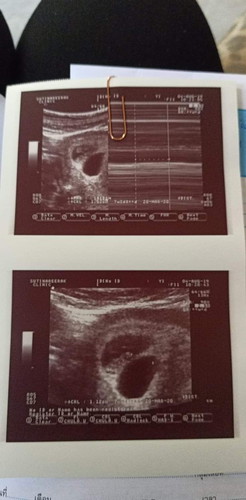

บ้านนี้ซาวด์ตอน 7w+4d มี2ถุงตั้งครรภ์ แต่คุณหมอเห็นมีเด็กอยุ่แค่ถุงเดียว มีโอกาสที่จะได้น้องแฝดมั้ยคะ หมอนัดตรวจอีกทีอีก 2อาทิตย์ค่ะ